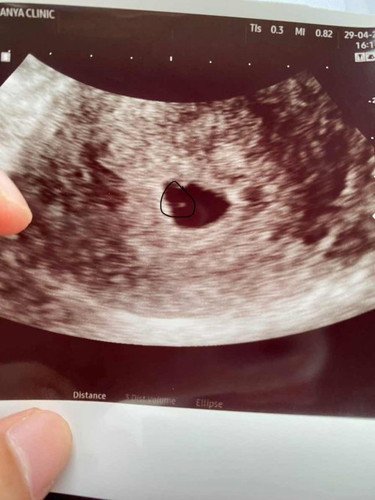

อัลตราซาวด์5 วีค

ตอนนี้ท้องได้5 วีค เเล้วค่ะเจอเเต่ถุง ที่วงๆไว้จุดสีขาวเล็กๆใช่ตัวน้องไหมคะ ท้องเเรกกลัวท้องลมมากเลยค่ะ#ท้องแรกคะ

เราเพิ่งซาวด์ไปตอน 6 week เป็นภาพเดียวกับแม่เลย หมอบอกจุดแบบนี้เป็นเหมือนถุงอาหารของลูก ยังไปเจอตัวลูกค่ะ หมอเลยนัด 8 week มาตรวจอีกทีค่ะ

5w ปกติจะไม่เจอตัวอ่อนค่ะ แม่อดทนรอทำใจสบายๆนะคะ จะเจอน้องช่วง 6-8 วีคค่ะ ถ้ารอบเดือนยาว ก็จะเจอน้องช้ากว่าคนอื่นหน่อยค่ะ

น่าจะใช้น่ะค่ะของเราหมอก็บอกว่าสีขาวเป็นวงกลมคือตัวน้องค่ะ

ของเรา 5w เจอแต่ถุง 8w ถึงเจอตัวน้องค่ะ